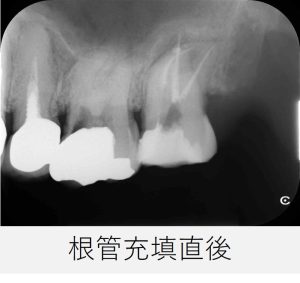

- 根管充填を行い、仮封しました。

レントゲン撮影で、根管充填の状態が良好であることを確認しました。

根管充填後は、画像と症状の両面から経過を確認していきました。

根管充填後から8カ月

- 痛みはなく、鼻の症状も認められませんでした。

- レントゲンおよびCT撮影を行い、根尖部の黒い影が縮小し、骨の回復傾向が確認されました。